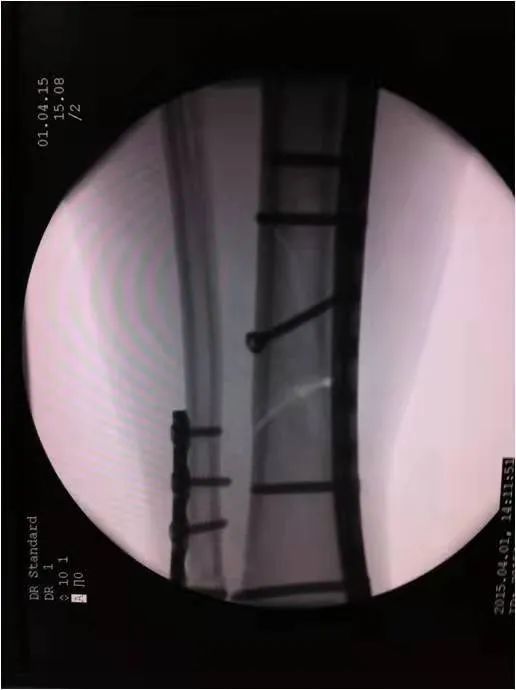

如采用傳統(tǒng)手術(shù)需大范圍剝離軟組織,手術(shù)切口在18公分,損傷面大,影響骨折愈合。經(jīng)過科內(nèi)術(shù)前討論后與患者及家屬溝通后,呂國福主任決定行小切口微創(chuàng)鈦板植入內(nèi)固定手術(shù)治療,術(shù)中植入內(nèi)固定物并剝離軟組織,此方法對(duì)周圍皮膚破壞小,手術(shù)切口最小僅0.5公分,極大降低皮膚壞死及后期出現(xiàn)骨不連發(fā)生幾率,從而達(dá)到解剖復(fù)位。

在急診科,檢驗(yàn)科,麻醉科共同努力下,僅用一小時(shí)完成整個(gè)手術(shù),術(shù)中出血量少、過程順利,手術(shù)非常成功。術(shù)后,呂國福主任數(shù)次查房,仔細(xì)查看患者的傷口愈合情況,關(guān)心患者的心理狀態(tài),為患者樹立信心,鼓勵(lì)患者進(jìn)行功能鍛煉。